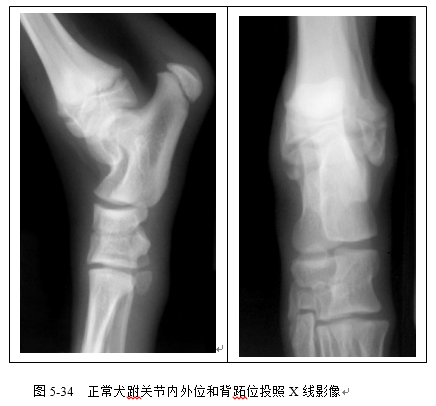

(3)识别胫腓骨、股骨、跗关节、膝关节X线影像(图5-32、5-33、5-34、5-35)。